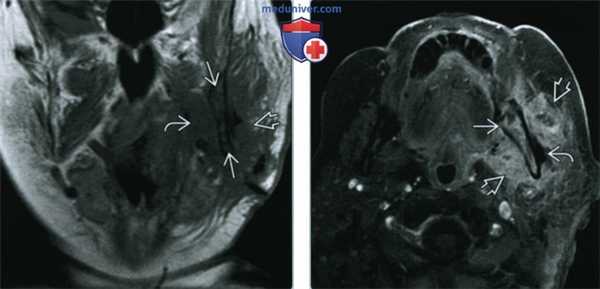

(Слева) На корональной КТ в костном окне у ребенка визуализируются обширные периостальные наложения, полностью окружающие ветвь нижней челюсти слева. Определяется частичная резорбция кортикальной пластинки нижней челюсти, которая, тем не менее, остается различимой. Также определяются деструктивные и склеротические изменения трабекулярной кости.

(Справа) На КЛКТ (профильный срез) у пациента с переломом нижней челюсти сращение отсутствует, определяется остеомиелит. Наблюдается разрежение и секвестрация язычной кортикальной плааинки, также видны периостальные наложения по нижнему краю.

(Слева) На корональной МРТ (Т1 ВИ) у пациента 79 лет с рецидивирующим абсцессом жевательного пространава через 12 недель после установления диагноза и дренирования определяется тотальное замещение гиперинтенсивного сигнала в жировом костном мозге нижней челюсти слева, сопоставимое с остеомиелитом.

(Справа) На аксиальной MPT (Т1ВИ С+) с жироподавлением у этого же пациента определяется диффузное контрастное усиление костного мозга и жевательного пространства (флегмона) слева. Определяется небольшой абсцесс в наружных отделах.

(Слева) Корональная МРТ в режиме Т1 у пациента 79 лет с рецидивом абсцесса жевательного пространства спустя двенадцать месяцев после того, как он был обнаружен и дренирован. Гиперинтенсивный сигнал, которым характеризуется костный мозг в норме, в нижней челюсти слева не определяется: изменения обусловлены остеомиелитом. Обратите внимание на отек медиальной крыловидной и жевательной мышц.

(Справа) При МРТ Т1ВИ FS c КУ в аксиальной проекции у этого же пациента определяется диффузное накопление контраста в коаном мозге слева, а также в жевательном пространстве (флегмона); виден небольшой абсцесс снаружи от нижней челюсти.